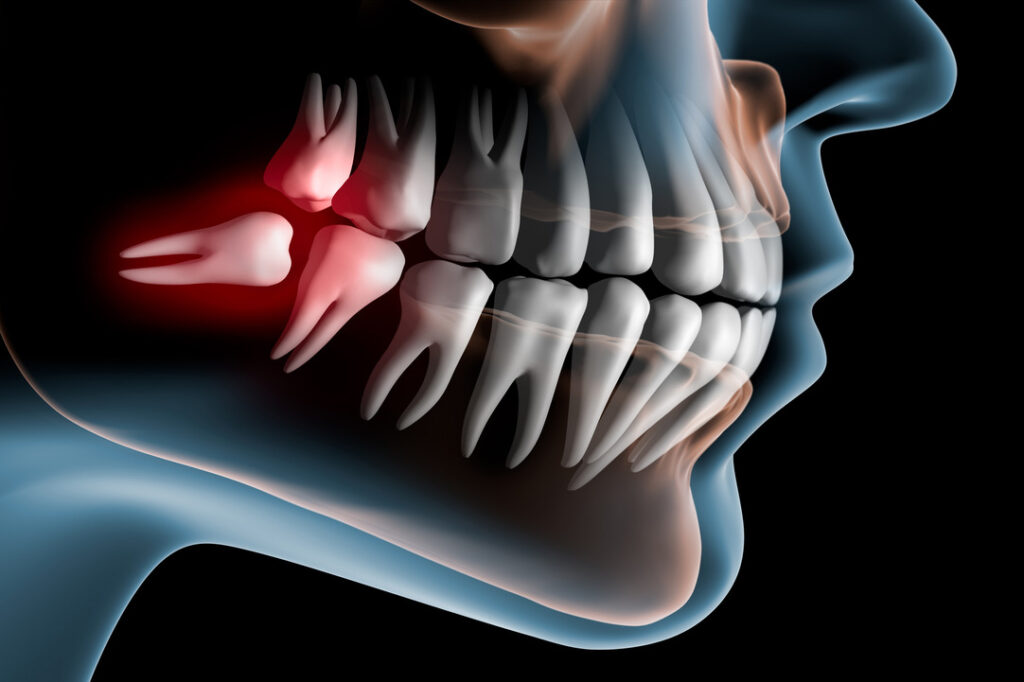

Wisdom Teeth Management

Safe and effective removal of problematic wisdom teeth.

Impacted Teeth Management

Surgical care for teeth trapped beneath the gums.